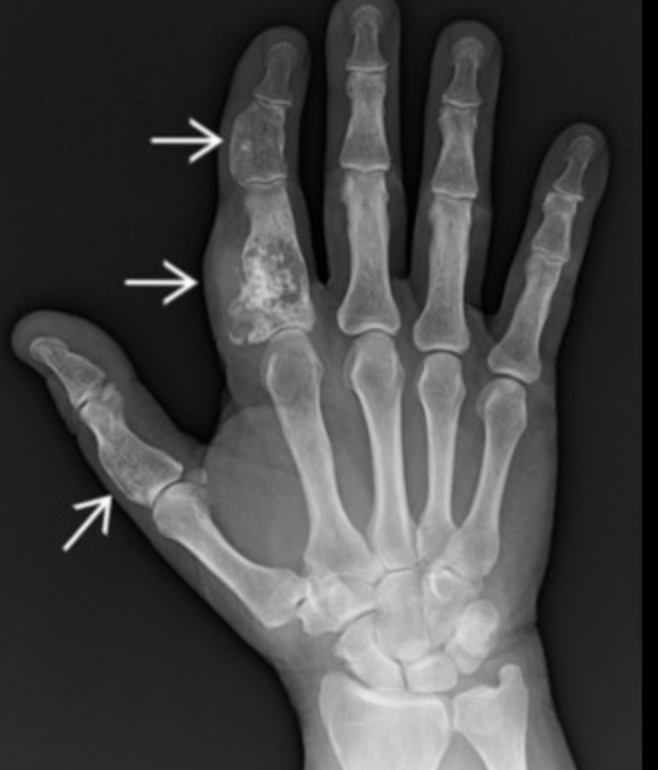

• Ollier’s Syndrome

• Multiple hand enchondromas

• No increased risk of cancer

• Maffucci Syndrome

• Multiple hemangiomas (look like phleboliths)

• Increased risk of cancer